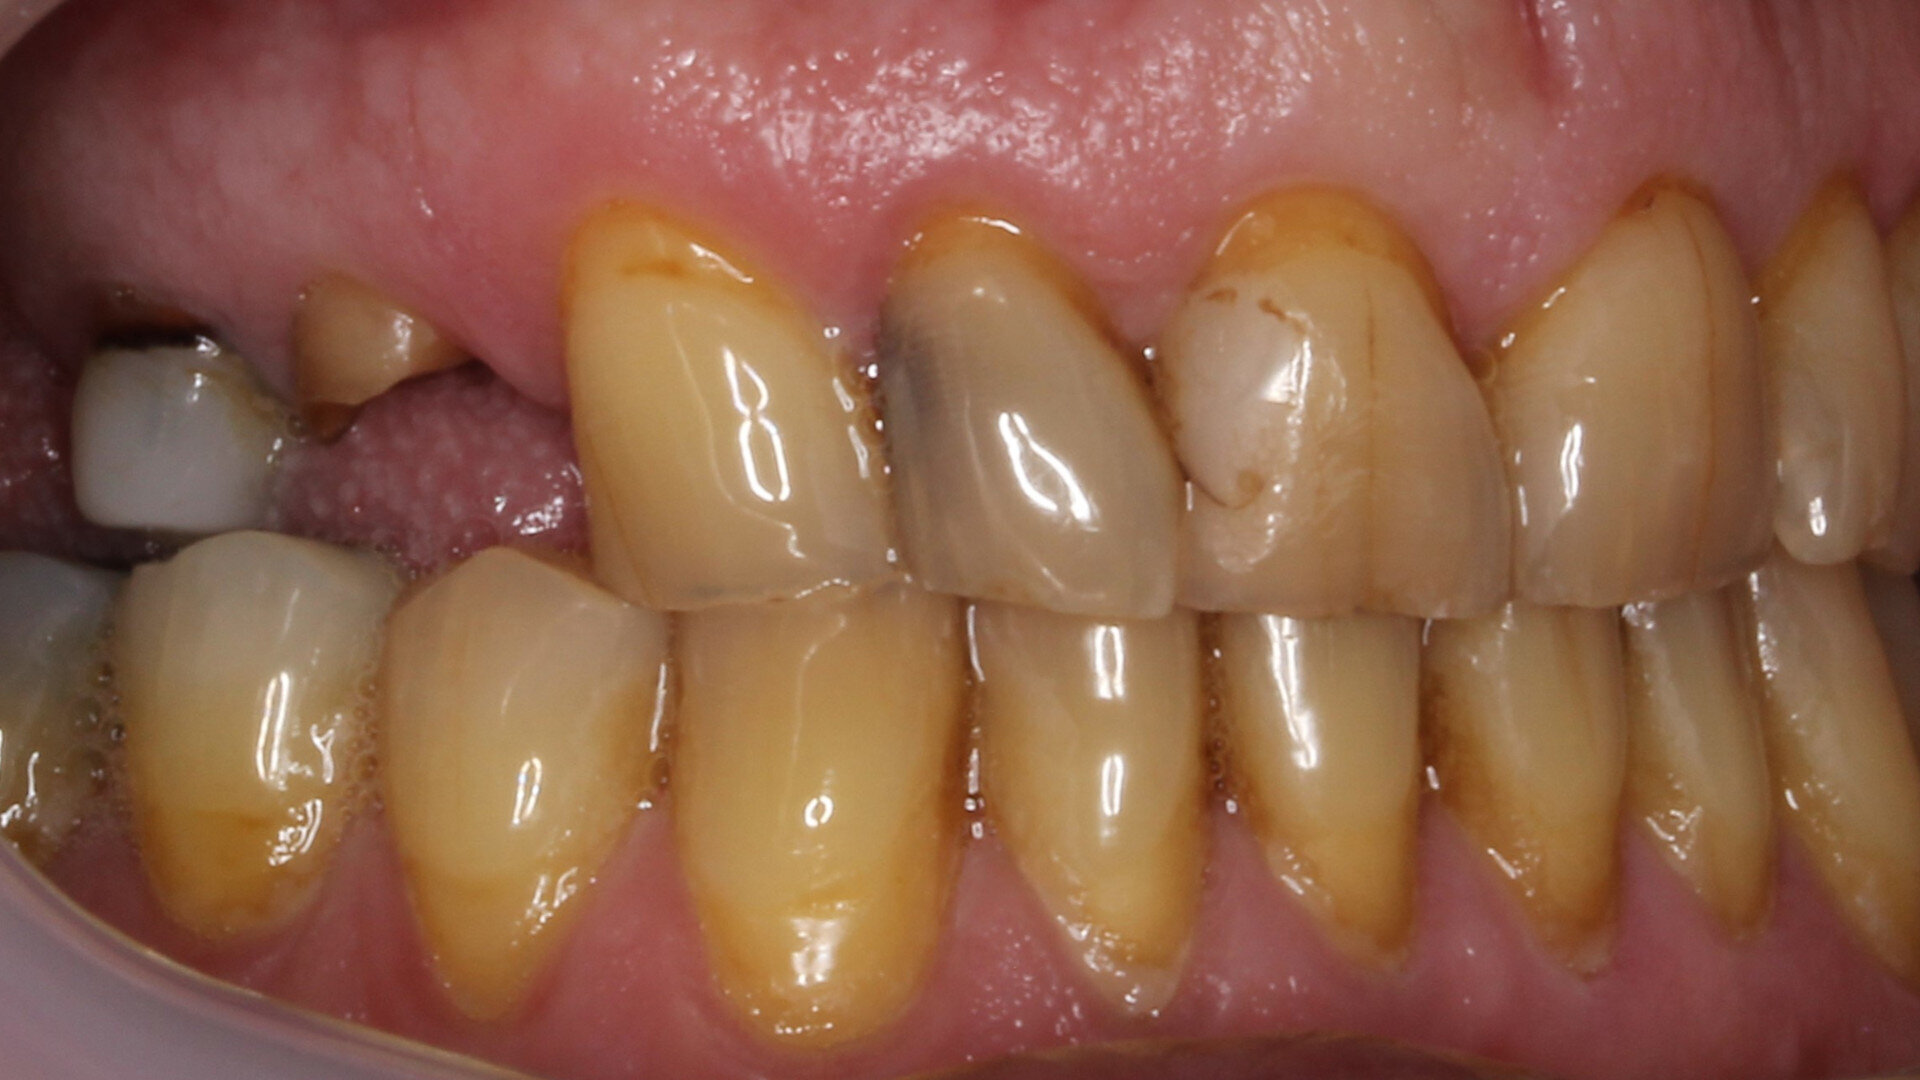

A male patient presented in our dental office with a severely broken maxillary right first premolar (tooth #14) that had been designated for extraction a number of years before. The tooth immediately distal (tooth #15) was also in need of substantial dental treatment (Figs. 1 & 2). The patient had hypertension that was controlled with anti-hypertensive medication, but was otherwise medically fit. He intended to have the colour of his anterior teeth improved, but wished to address the issues on his maxillary right side first.

Tooth #14 was deemed unrestorable, and so it was decided to extract the tooth (Figs. 3 & 4), wait for bony healing and replace it with an implant with a provisional restoration. During the healing process, endodontic therapy would be performed on tooth #15. After bony integration, implant #14 would be restored with a screw-retained direct-to-implant zirconia crown, and tooth #15 would also be restored with a complete zirconia crown. A deliberately lighter shade would be chosen, factoring in the patient’s long-term desire to improve the colour of his teeth.

Fig. 2: Pre-op situation, showing the maxillary right first premolar with a poor restorative prognosis.